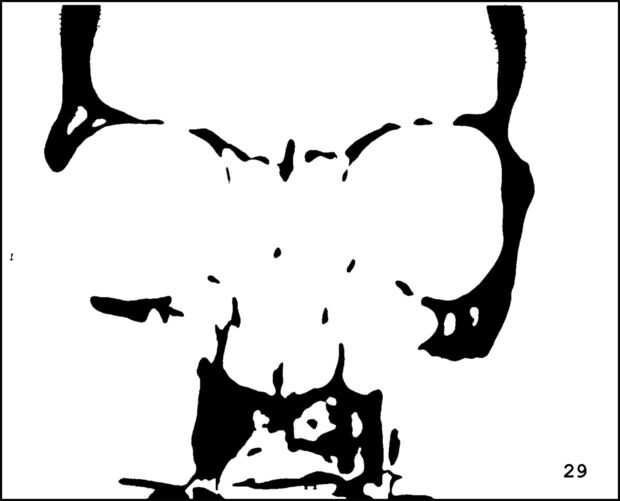

¡ Wow! Este fue por menos de 12 horas y tengo 1.000 visitas! Esto es sólo mi segundo instructable, así que estoy encantada. Decidí seguir adelante y publicar las imágenes que utiliza. Se trata de MRI de mi esposa, así que ella sólo puede tener lo mundos primer código abierto jefe. Mi lámpara utiliza solamente las primeras 16 capas, pero te di todos 34 que representa. Seguir adelante y usar estas imágenes, pero si lo haces, por favor me manden una imagen de lo que te ocurrió así que puedo hacerla sentir un poco famoso. ¡Que te diviertas!